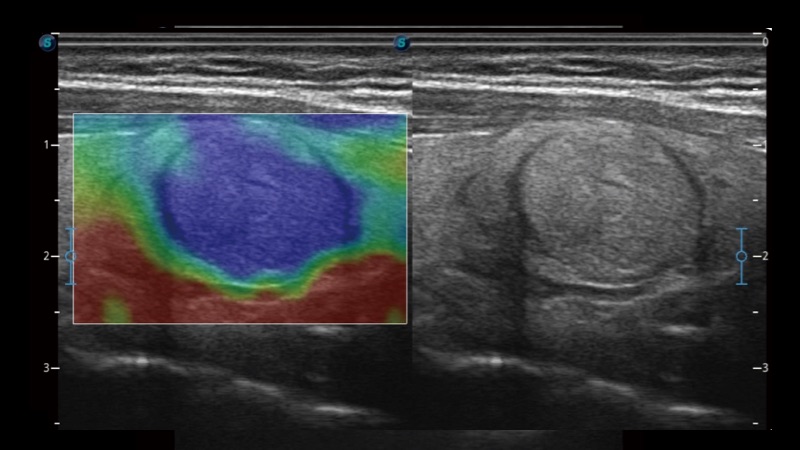

開立醫(yī)療通過不斷的技術(shù)創(chuàng)新,為大眾的生命健康提供持續(xù)關(guān)愛。P12 Plus采用全新一代超聲成像平臺(tái),新平臺(tái)旨在將真實(shí)還原組織解剖結(jié)構(gòu)作為首要目標(biāo)。平臺(tái)采用全新集成化硬件模塊,搭載新一代芯片,系統(tǒng)性能得到大幅提升,為您的診斷提供了豐富的臨床信息。優(yōu)異的圖像表現(xiàn),豐富的探頭配置,全面的應(yīng)用功能,為您日常診斷提供了可靠的助手。